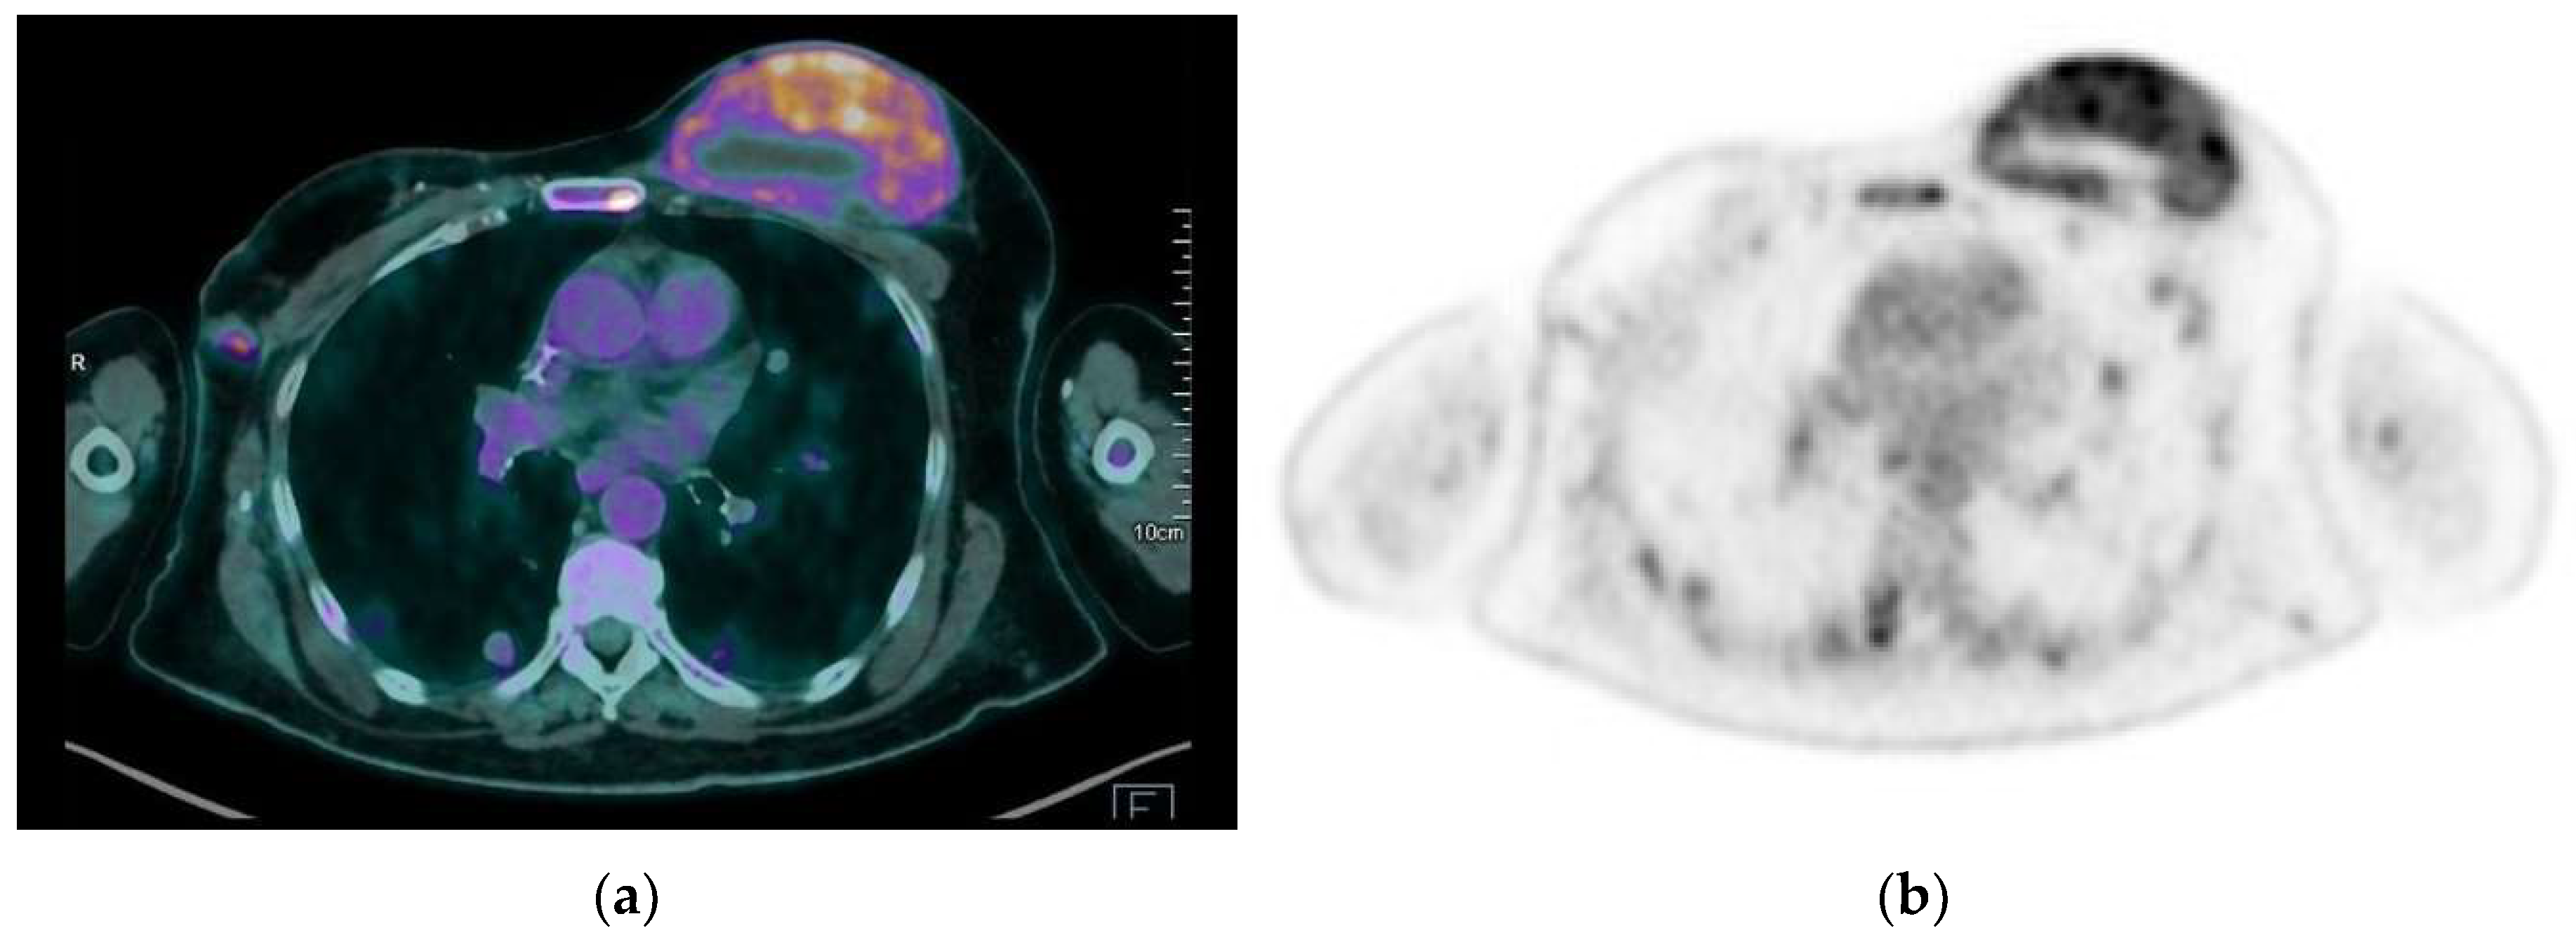

4.5. PET-CT